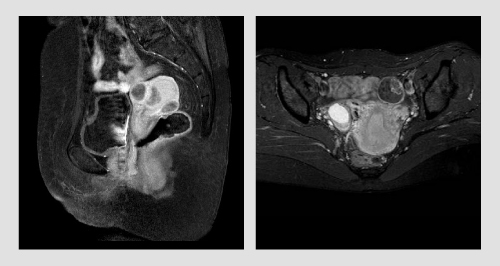

MRI骨盤検査では、子宮・卵巣・膀胱の検査を行い、下記のような病気を発見することが出来ます。

子宮頚部癌・子宮体部癌・子宮筋腫・子宮内膜症・卵巣のう腫・卵巣癌・膀胱癌など。